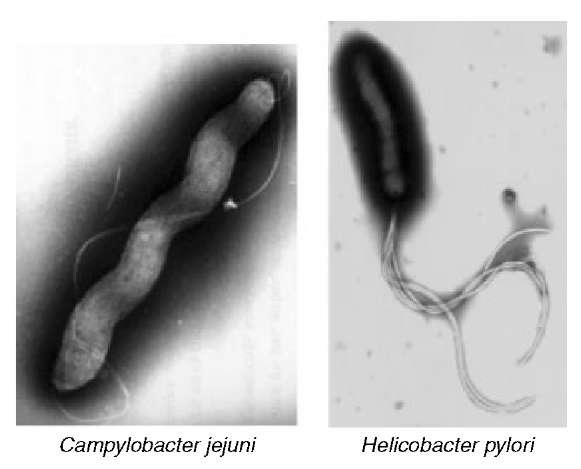

Кампилобактер фетус: патогенез и инфекции